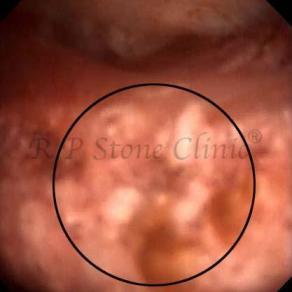

These images are taken as snap shots from the video recording of RIRS Surgery done at our hospital. These are Randall’s Plaques seen with Digital FLEX XC & Digital FLEX XC S. The cream or whitish patches are seen on the tips of RENAL PAPILLAE as seen in images below.

The Below Images Show Small Stones attached to the Renal Papillae.